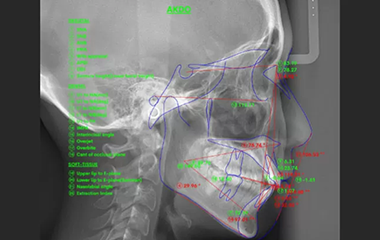

矯正治療を成功に導くには、歯科医師の経験と技術はもちろん、歯科用CTやセファログラム(頭部X線)、口腔内スキャナーなど、精密な診断と治療計画に必要な設備も欠かせません。

精密なデジタル診断を実施

当院では、口腔内スキャナーや3D画像解析、AIによる分析などの先進のデジタル技術を駆使して、正確でブレのない診断を行っています。精密なデータに基づく治療計画を立てていきます。